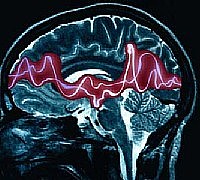

Scopo del corso è la conoscenza approfondita di alcune sindrimi epilettiche che rappresentano spesso una sfida sul piano della diagnosi e della terapia o perché varianti atipiche o perché di recente descrizione. È il caso delle forme atipiche delle Epilessie parziali idiopatiche dell’infanzia, delle Epilessie temporali laterali. Un altro campo di interesse è l’Epilessia correlata a tumori celebrali, con le sue sfide terapeutiche.

La conoscenza teorica e il corretto iter diagnostico da applicare in questi casi sono indispensabili. Pertanto, sessioni teorico-pratiche interattive, con presentazione dei casi clinici e delle registrazioni video-EEG, condurranno alla diagnosi, alla formulazione della prognosi e all’impostazione della terapia.